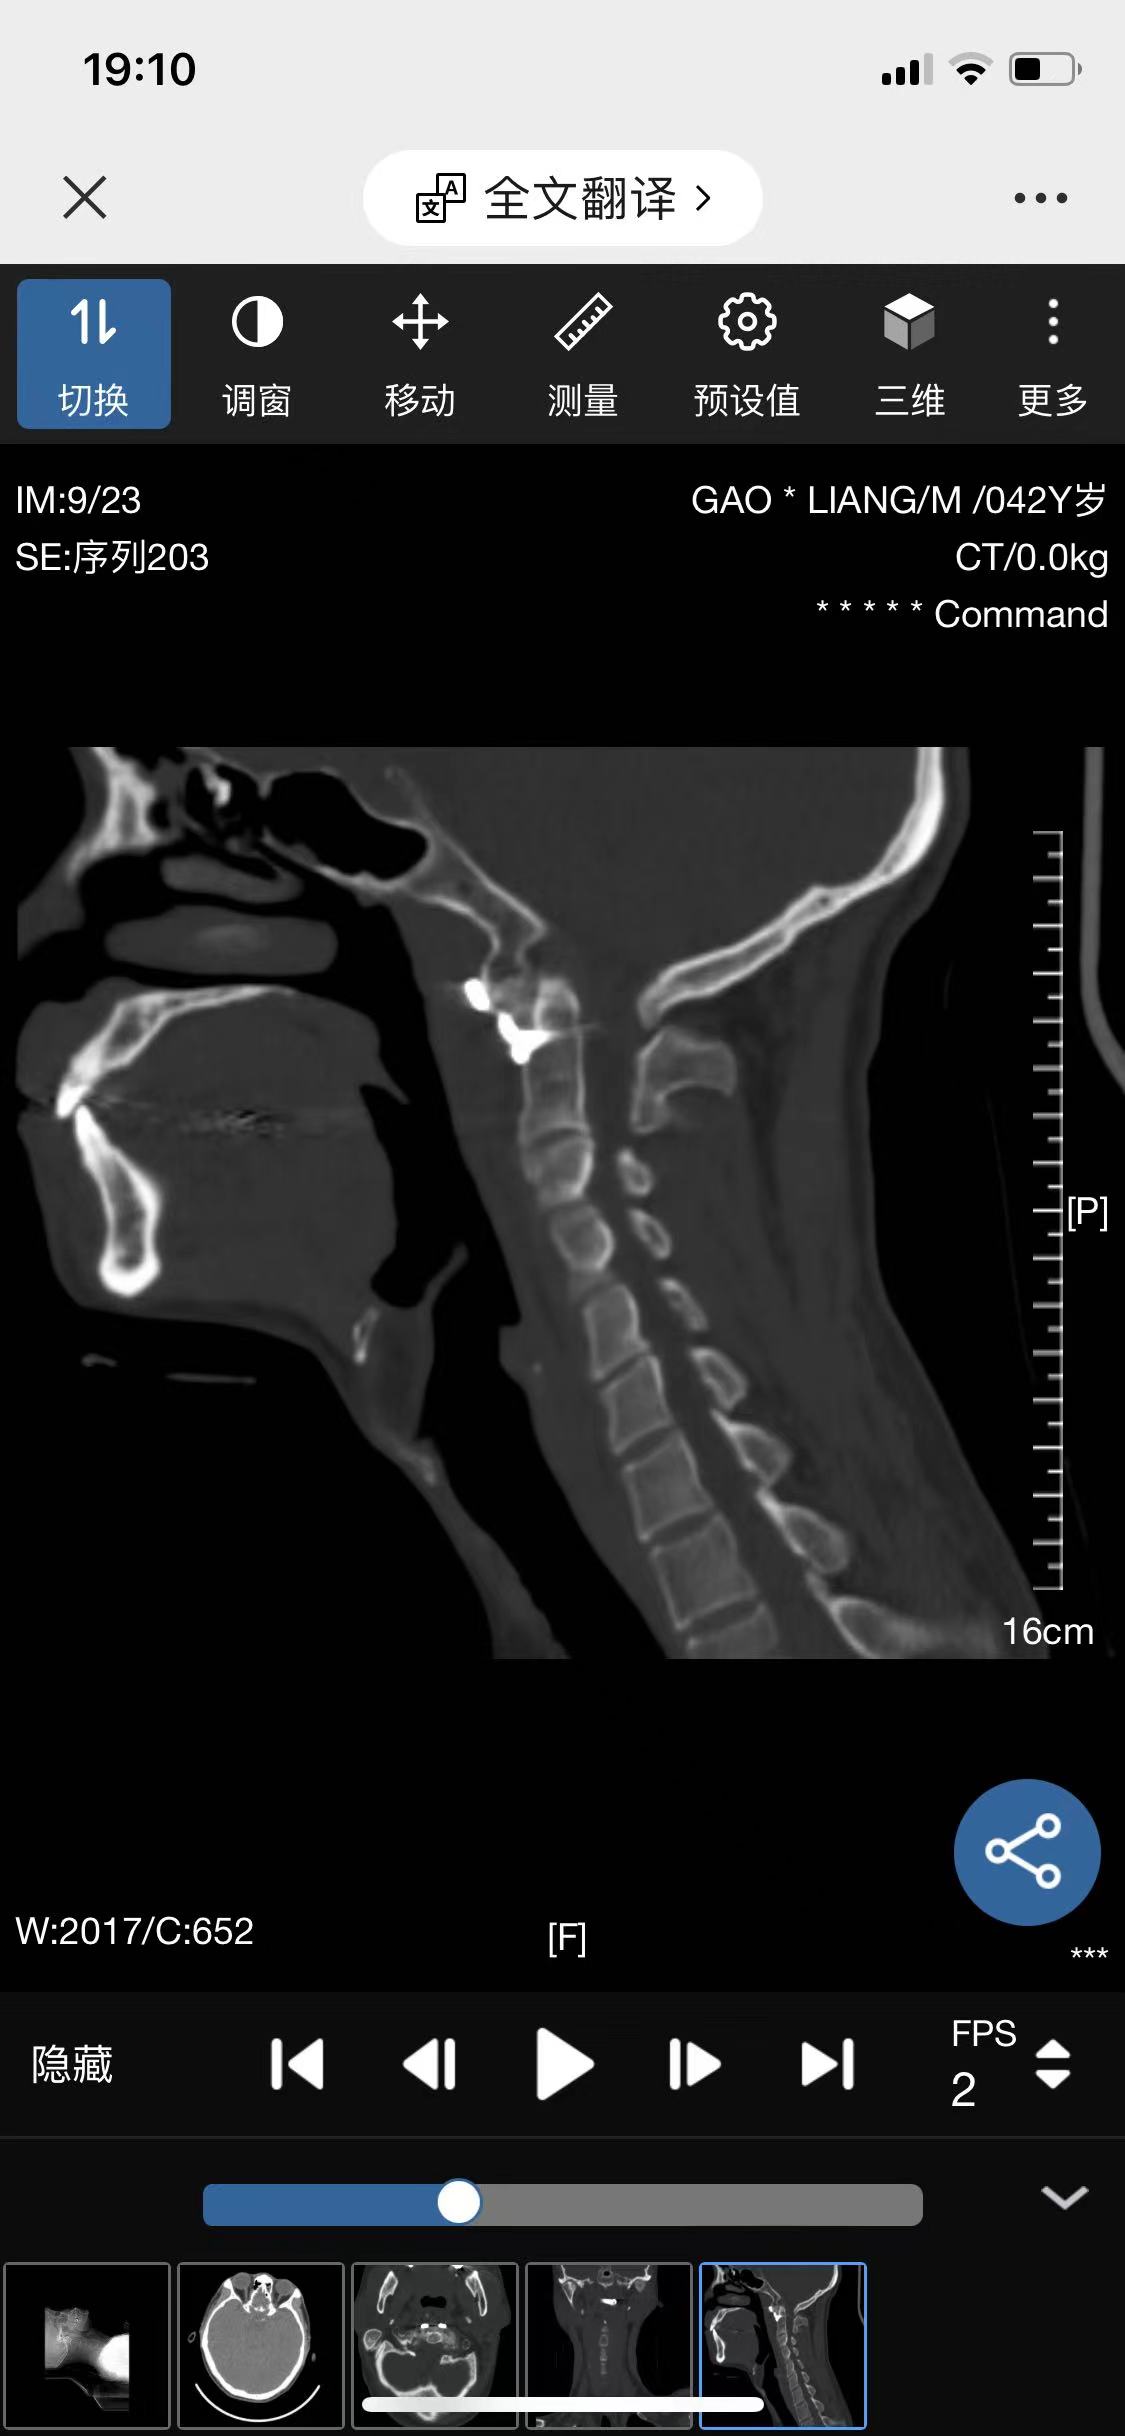

• 诊断:寰枢椎脱位

• 影像:

• 术后影像: